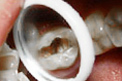

• 蛀牙

树脂补牙案例展示 TAIKANG BYBO DENTAL